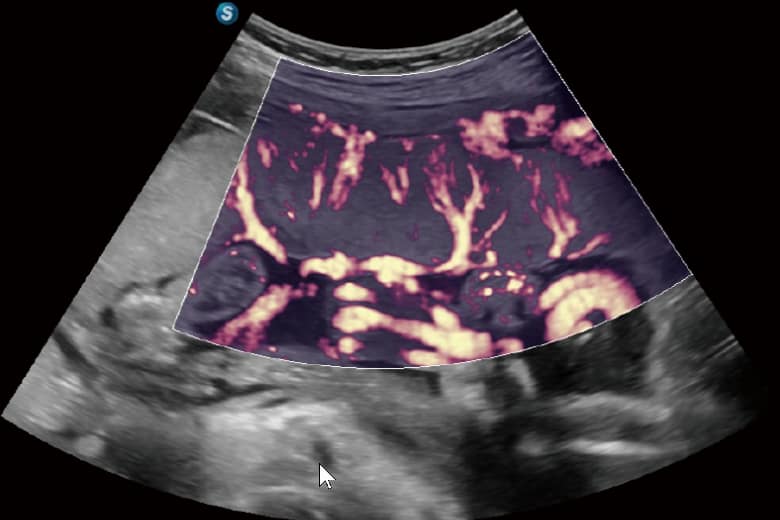

• Bright Flow: Erzeugt eine 3D-ähnliche Darstellung des Farbdopplers ohne Volumenwandler, was die Abgrenzung von Gefäßwänden verbessert.

• Micro F: Trennt subtile Blutflusssignale effizient von Gewebebewegungen, um die Mikrozirkulation präzise darzustellen.

• FHR: Erhöht die Empfindlichkeit bei der Beobachtung mikrovaskulärer Strukturen in Organen.